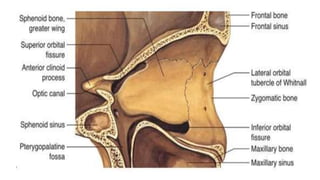

Orbital Roof

• Frontal Bone

• Sphenoid Bone

Medial Wall

• Closest to nose ‘SMEL’

• Maxillary bone

• Ethmoid bone

• Lacrimal bone

Lateral wall

• “Great Z”

• Greater wing of sphenoid

• Zygomatic bone

Orbital floor

• Look down to “Zip My Pants”

• Palatine bone